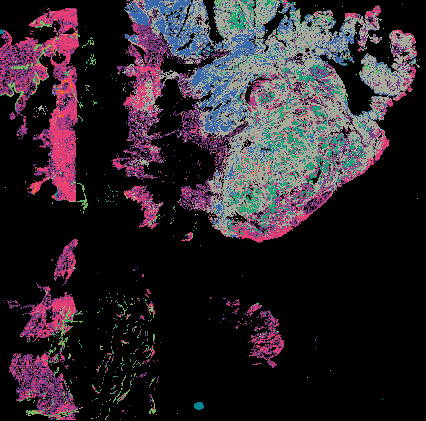

Serous Tubal Intraepithelial Carcinoma (STIC) with BRCA2 Mutation (LSP18251) from 'Multimodal Spatial Profiling Reveals Immune Suppression and Microenvironment Remodeling in Fallopian Tube Precursors to High-Grade Serous Ovarian Carcinoma'.